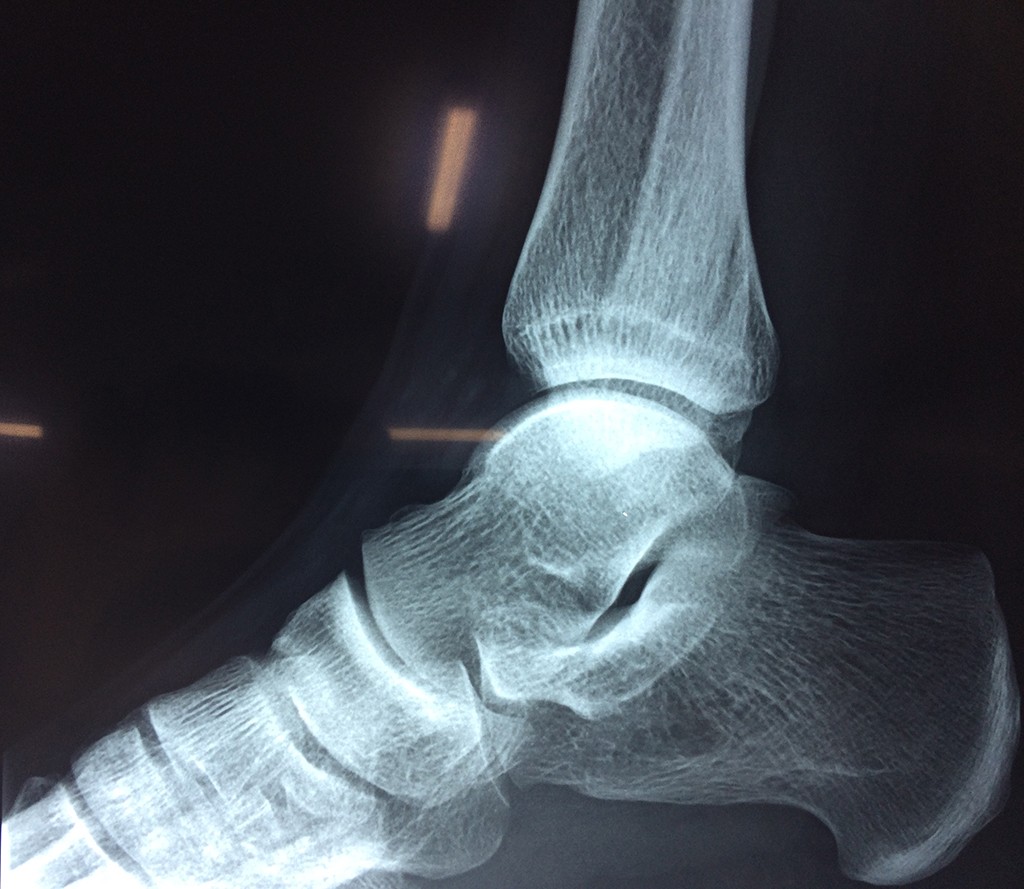

Una fractura de tobillo es la rotura de uno o más de los huesos del tobillo. Estas fracturas pueden ser:

Algunas fracturas de tobillo pueden requerir cirugía si:

- Los extremos de los huesos están desalineados entre sí (desplazados).

- La fractura se extiende hasta la articulación del tobillo (fractura intra-articular).